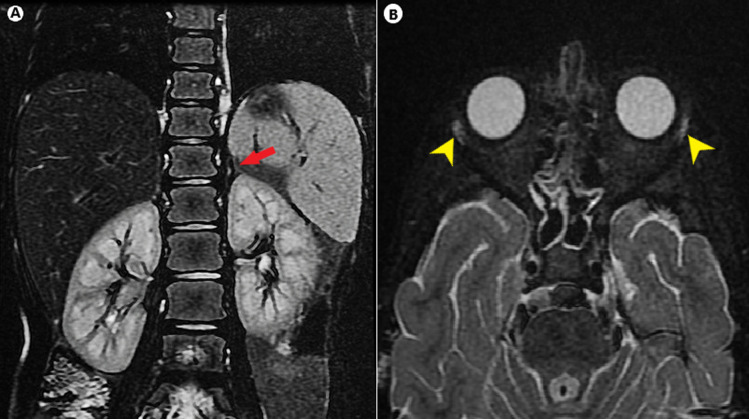

Allgrove syndrome (AS), an uncommon multisystem disorder, is characterized by the classic clinical triad of alacrimia, achalasia, and adrenal insufficiency, and is typically limited to glucocorticoid deficiency with preserved mineralocorticoid (MC) function. Here, we present the case of a 5-yr-old girl with alacrimia since birth, failure to thrive, and generalized hyperpigmentation for the past two years, who presented to the emergency department with an altered sensorium. Upon admission, the patient was found to have hypoglycemia and hyponatremia. After subsequent evaluation, the patient was diagnosed with phenotypically incomplete AS with mineralocorticoid insufficiency and harbored a novel homozygous mutation in exon 7 of the AAAS gene (c.618del; p.Ser207LeufsTer84). Treatment with hydrocortisone and fludrocortisone yielded remarkable outcomes. Given the variable presentations of this condition, a high index of clinical suspicion and awareness of atypical features are essential for early diagnosis and initiation of coordinated care to prevent unnecessary morbidity and mortality. When AS is suspected, molecular genetic testing should be performed to confirm the diagnosis, plan management, and provide genetic counseling.